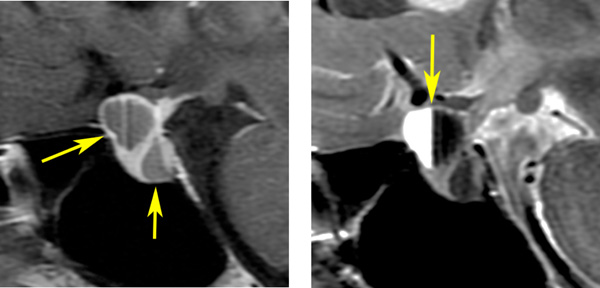

ラトケのう胞はT1強調画像で白く(左:高信号)にみえて,T2強調画像で黒く(右:低信号)にみえることもあります。前の例とはかなり違った印象です。中身は乳白色のドロドロの液体です。矢印のところは視神経交叉(左右の視神経がつながるところ)で,ラトケのう胞に圧迫されて弓形に変形しています。このくらいの視交差の変形では視野障害は出ませんし視力も低下しません。ですから,手術も何もしないで経過観察のみをします。多くの場合は,何も治療しなくて良いものです。この患者さんは無治療で経過を見ました。

この画像はプロラクチンが上昇 (51ng/ml) して生理不順になった20代女性のものです。プロラクチン産生腫瘍には見えません。左の画像では嚢疱が2つ見られます。右の画像では,上の嚢疱に液面 fluid-fluid levelが見られて,腫瘍内の出血があったようにもみえます。手術後の病理診断は両方共にラトケのう胞でした。プロラクチン値は正常に戻りました。

でも手術中の所見では,上方のものは黄色肉芽腫のようで,のう胞内用液は頭蓋咽頭腫のように廃液用のドロッとした暗緑褐色のもので,さらにキラキラ光るコレステリンの結晶がたくさん出てきました。下の嚢疱は黄褐色の通常のラトケのう胞の内容液でした。両方ともに下垂体の正常腺組織とは区別がつかない繊維化した壁があって,危うく下垂体機能損傷を生じるところでしたが難を避けました。